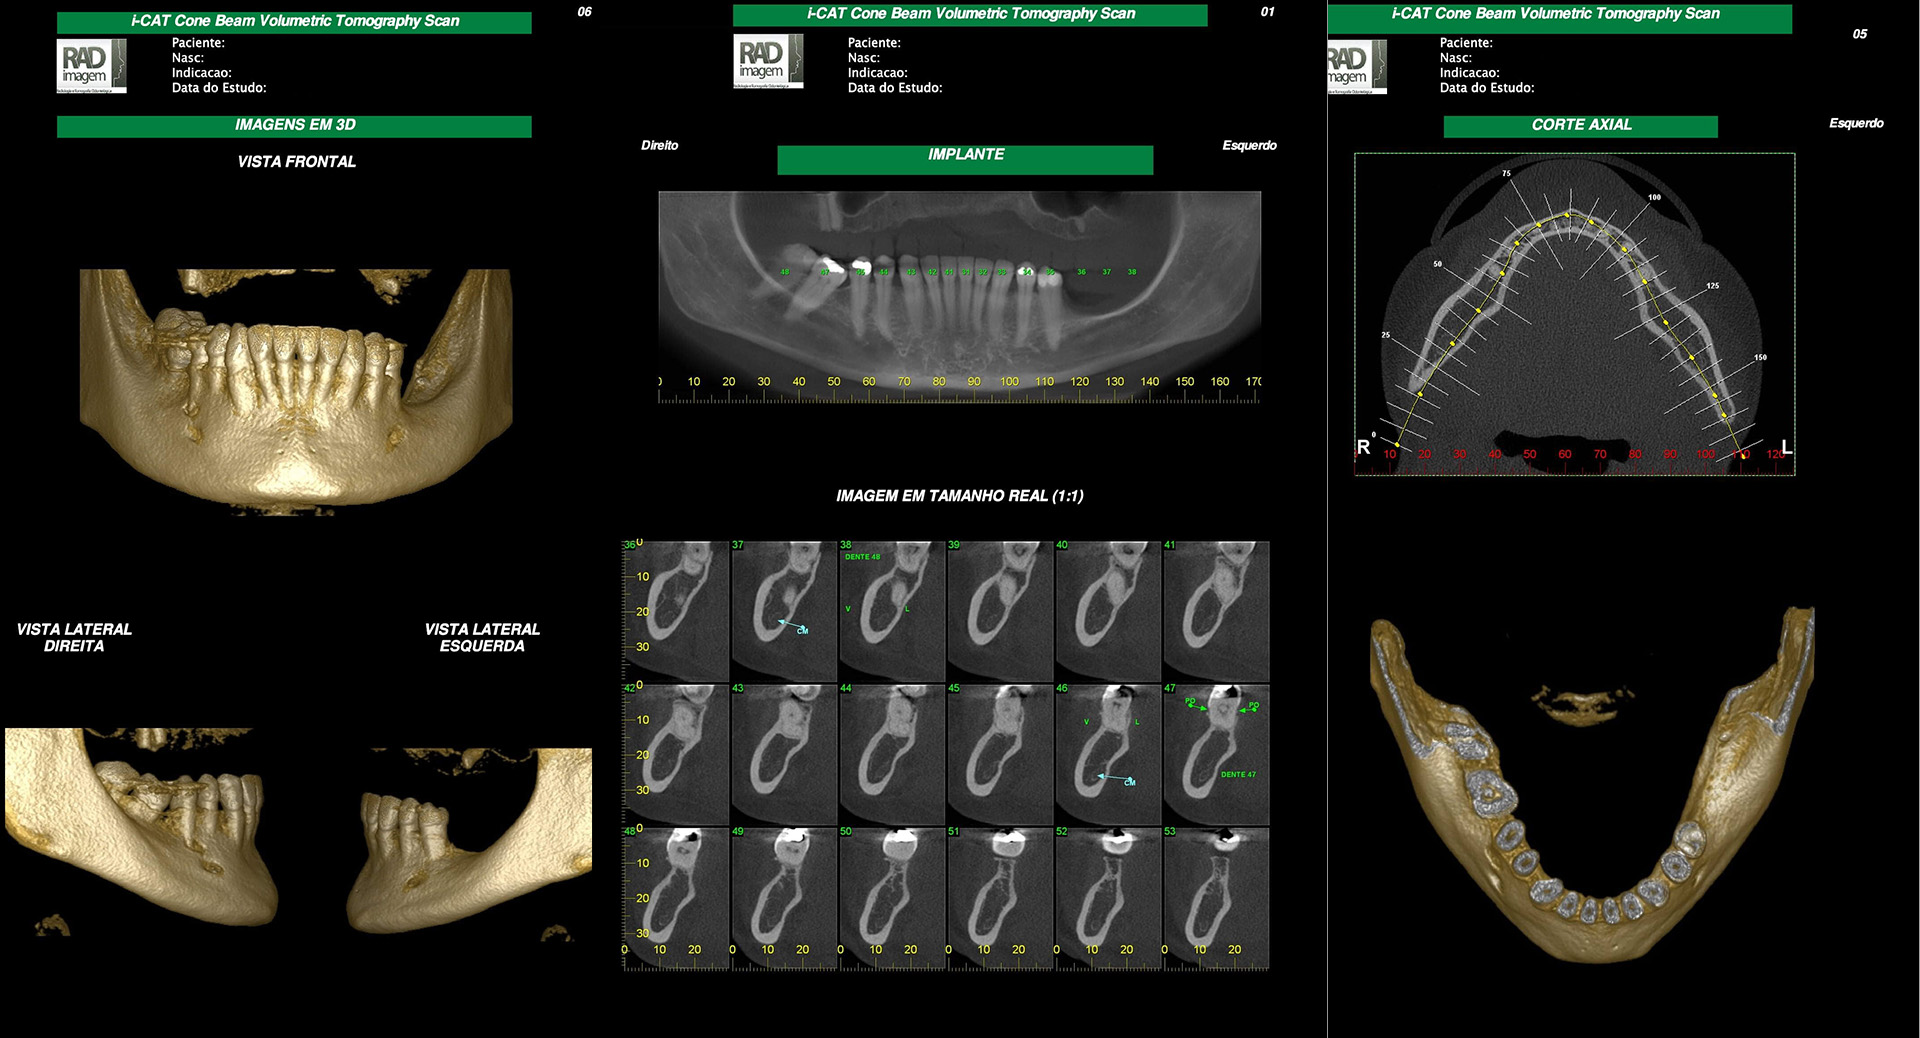

clinicas.cotanet.com.brOdonto.i Diagnósticos -Tomografia Odontológica E CAD-CAM.

clinicas.cotanet.com.brOdonto.i Diagnósticos -Tomografia Odontológica E CAD-CAM.

www.hojemais.com.brTomografia Odontológica Para Implantes Dentários • Odonto.i

www.hojemais.com.brTomografia Odontológica Para Implantes Dentários • Odonto.i